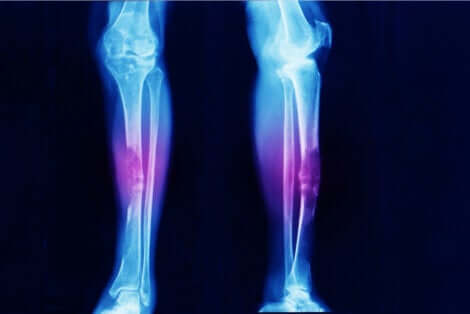

- Ostéosarcome : cancer des os.

Les sarcomes ne sont pas très communs. Diverses études signalent par exemple que, l’ostéosarcome (tumeur dans le squelette) représente seulement 0,2% de tous les cancers malins. Cela se traduit par une incidence de trois cas pour un million de personnes chaque année.

“Les ostéosarcomes et les sarcomes synoviaux sont des tumeurs malignes des os qui surviennent souvent près des genoux.”